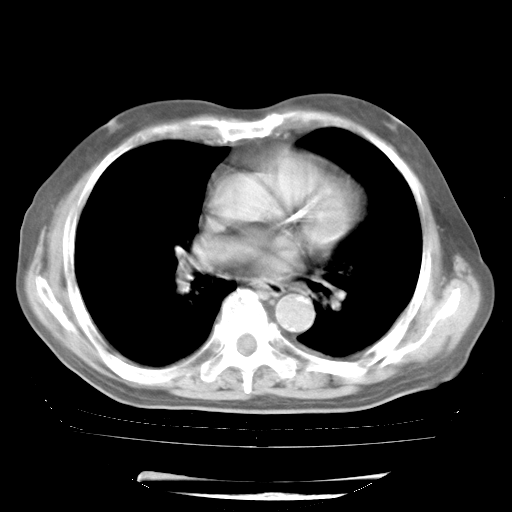

4月28日肺部CT——再次出现类似去年5月9日——磨玻璃样、间有“粟粒样”改变。